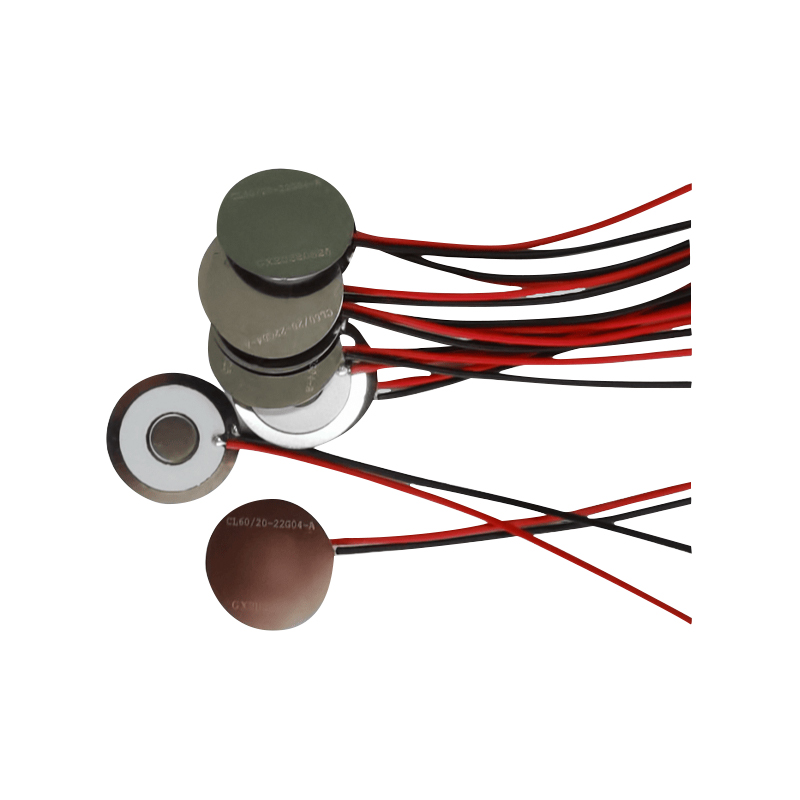

Lékařské síťové nebulizační tablety jsou přesné součásti používané v lékařských zařízeních k přeměně léků nebo roztoků na malé aerosolové částice pro léčbu různých respiračních poruch, jako je astma a chronická obstrukční plicní nemoc (CHOPN) atd. inhalací. Konstrukce a výběr materiálu vrstvy nebulizátoru je rozhodující pro zajištění účinného podávání léčiva a pohodlí pacienta. Nerezový membránový plech je v ocelovém plechu proražen tisíci malých 2-3μm síťových otvorů v ocelovém plechu pomocí technologie laserového vrtání v přesném laserovém procesu a poté je pevně spojen s piezoelektrickým keramickým kruhovým plechem, který převádí rezonanční frekvenci piezoelektrického plechu na vysokofrekvenční vibrační energii prostřednictvím výstupního signálu desky ovladače PCB a rychle rozbíjí kapalinu. léky na jemné aerosolové částice. Tyto kapičky se také nazývají střední velikost částic, když střední procento velikosti částic D50 dosáhne > 60 % nebo více, částice budou dostatečně malé, aby se mohly dýcháním dostat hluboko do plic k povrchu alveol, čímž se zlepší absorpční účinnost léku a terapeutický účinek. Micro mesh nebulizérový list Medical Mesh má hlavně několik forem, nerezový mikrosíťový nebulizační list, nikl-palladium lékařský nebulizační list, PI polymerový lékařský nebulizační list a tak dále. Všechny výše uvedené jsou prostřednictvím piezoelektrické keramické vibrační přeměny energie k dosažení atomizačního efektu.

Bezolovnatá piezoelektrická keramika je známá jako piezoelektrická průmyslová „perla“, v budoucnu postupně ve všech aspektech nahradí piezoelektrickou keramiku na bázi olova, která již má stejný piezoelektrický výkon, a piezoelektrický plech na bázi olova. Je zcela netoxický, nezávadný, bezpečný a šetrný k životnímu prostředí, neobsahuje olovo, antimon a další těžké kovy a další prvky s omezením Rohs, vysoká Curieova teplota Tc-328°C, velmi nízká elektrická ztráta TangentLoss Bezolovnatý piezoelektrický lékařský atomizační čip má proto velkou komerční hodnotu a univerzální hodnotu, skutečně netoxická a ekologická, bezolovnatá piezoelektrická keramika kromě neznečišťujících, piezoelektrických výkonů srovnatelných s keramikou na bázi olova, se stane oblíbenou piezoelektrickou keramikou šetrnou k životnímu prostředí. Po letech výzkumu a vývoje, po neustálém testování a experimentování, se společnosti podařilo vyrobit bezolovnatý lékařský atomizační čip tak, aby dosáhl stejného množství atomizace jako atomizační čip na bázi olova a stejných požadavků na průměr částic. Bezolovnatý lékařský nebulizační čip Mesh bude jistě zářit a získá širokou škálu scénářů použití.